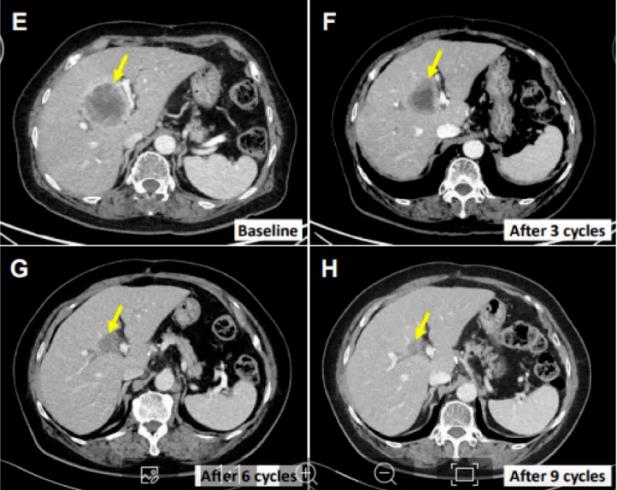

患者E0217

该例患者为76岁的女性,被诊断为肝外胆管癌,接受了胆总管分段切除和胆囊切除手术。四个月后,她发现了多个肝转移灶,并接受了吉西他滨和顺铂的全身化疗。随后,多处肝脏病变进展。在接受上述SMT-NK和帕博利珠单抗治疗后,她的肝转移病灶缩小了70.4%,并且在初次治疗12个月后仍未出现进展。